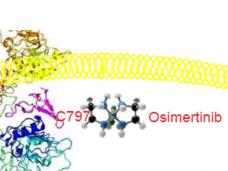

Osimertinib Improves Survival in Advanced Lung Cancer with EGFR Mutations

Osimertinib (Tagrisso) improves survival in people with non-small cell lung cancer with EGFR mutations, updated clinical trial results show. People treated with osimertinib lived longer than those treated with earlier-generation EGFR-targeted drugs.